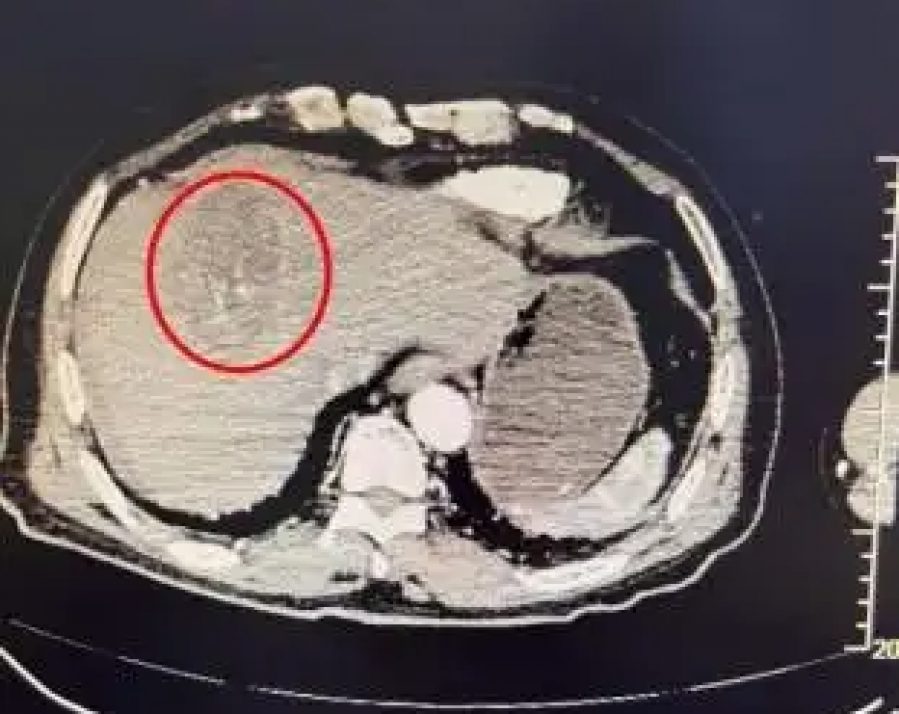

经急诊检查发现,她肝脏左叶存在一颗约96×68毫米的巨大肿瘤,且已经破裂,导致腹腔出现明显积血。结合既有病史,医生最终确诊为肝脏恶性肿瘤破裂出血,属于极为凶险的并发症。